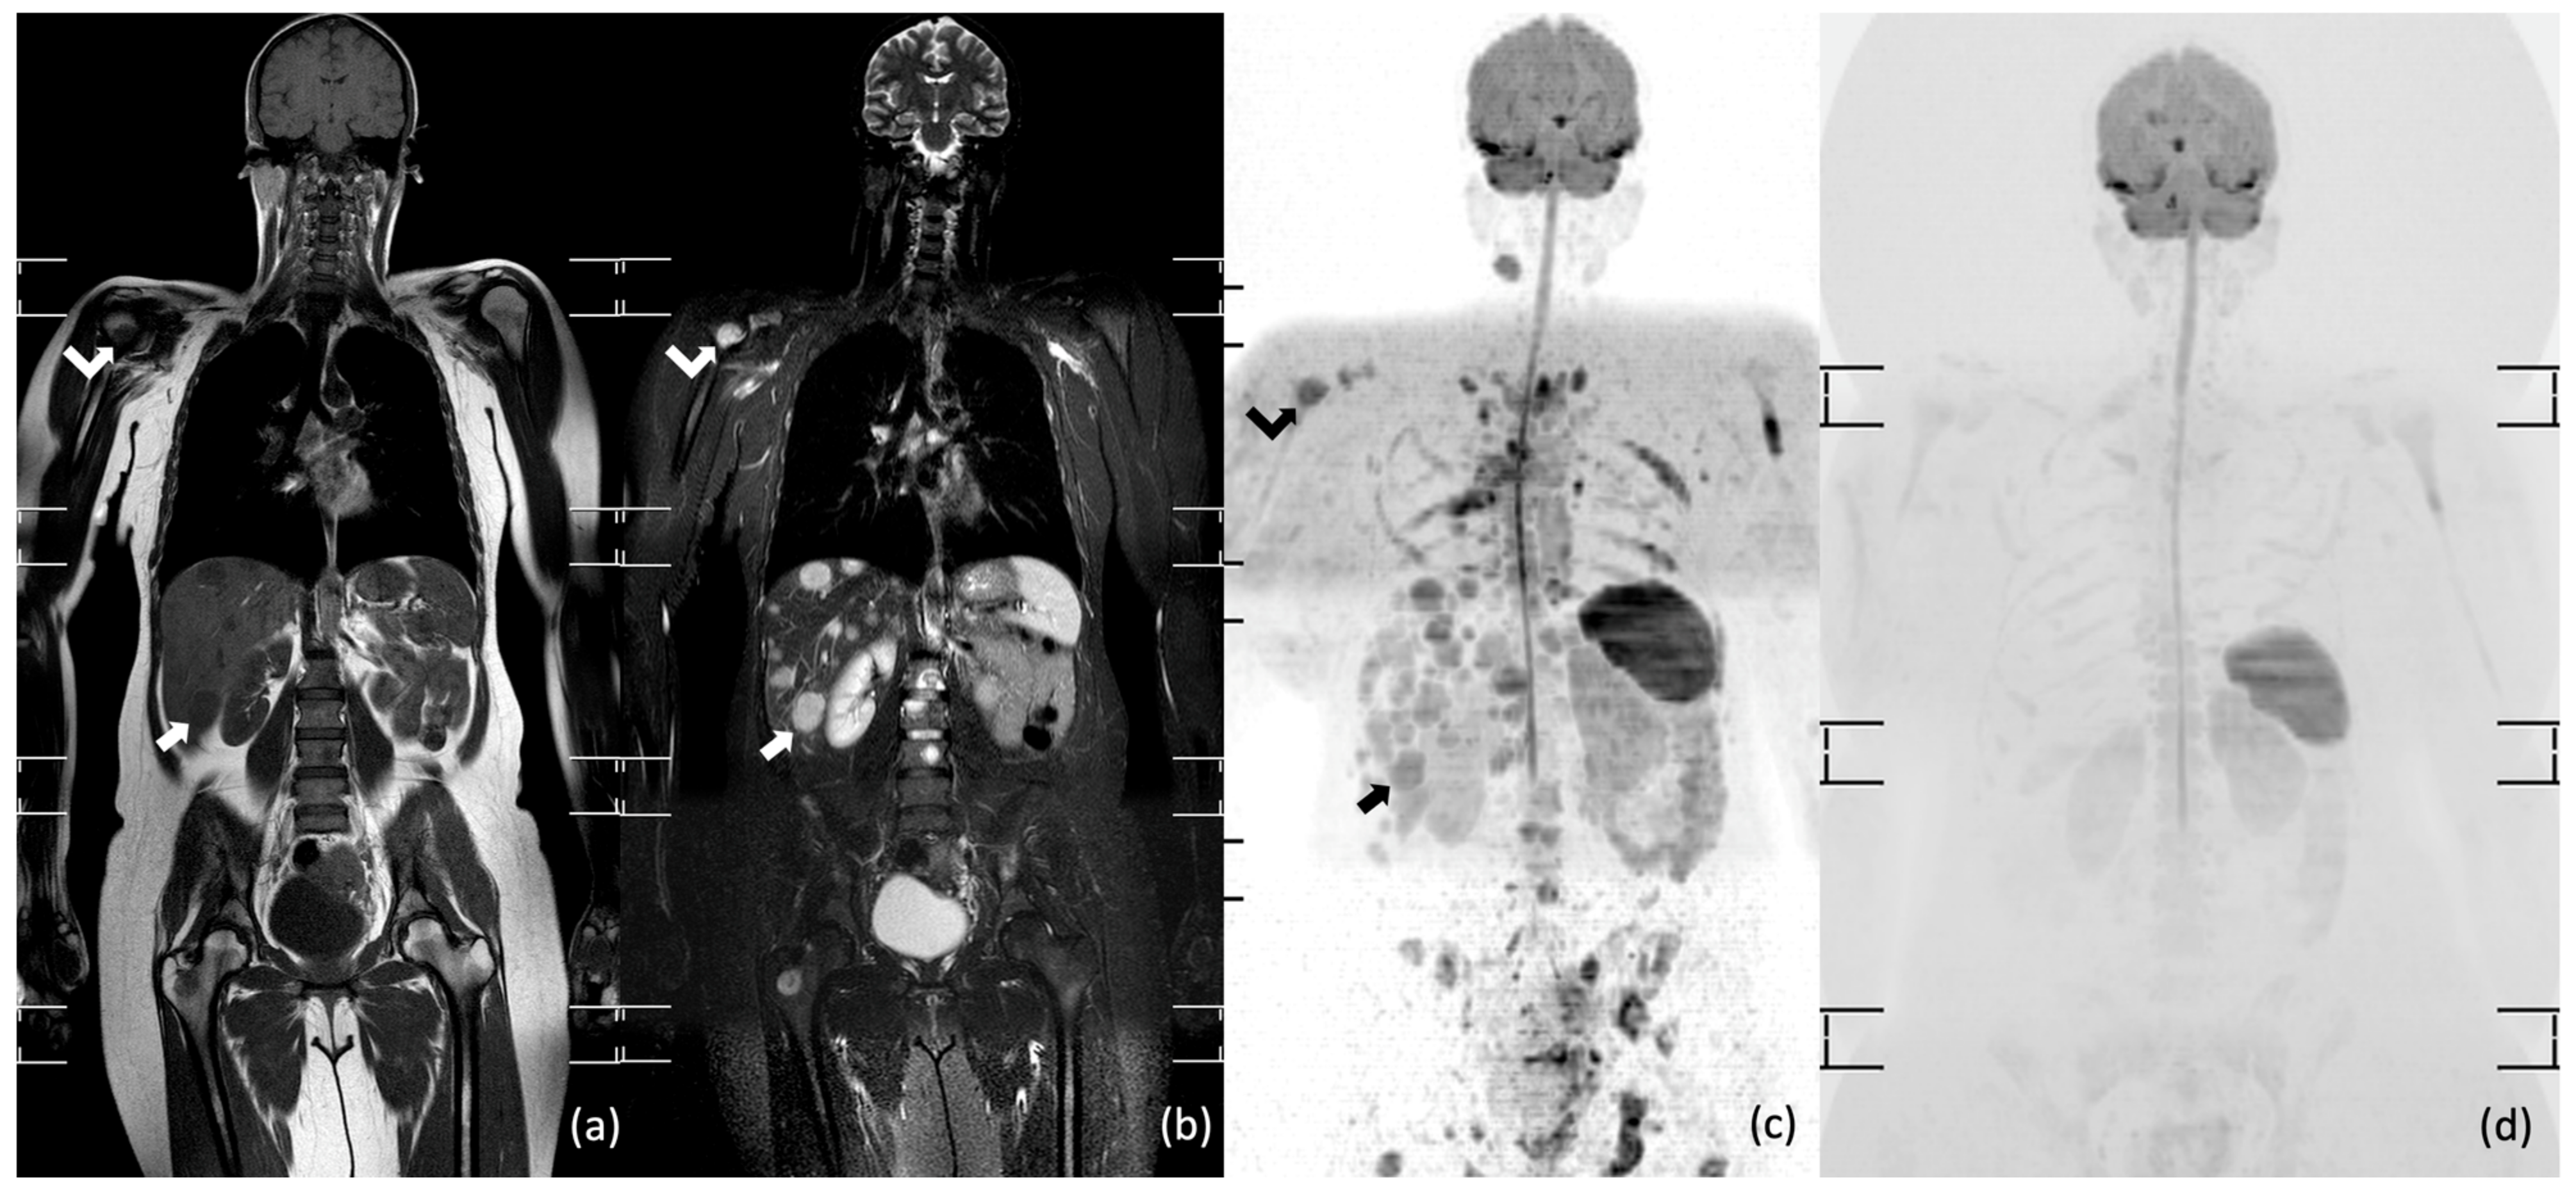

- Albano, D.; Patti, C.; Lagalla, R.; Midiri, M.; Galia, M. Whole-body MRI, FDG-PET/CT, and bone marrow biopsy, for the assessment of bone marrow involvement in patients with newly diagnosed lymphoma. J. Magn. Reson. Imaging 2017, 45, 1082–1089. [Google Scholar] [CrossRef]

- Adams, H.J.A.; Kwee, T.C.; Vermoolen, M.A.; De Keizer, B.; De Klerk, J.M.H.; Adam, J.A.; Fijnheer, R.; Kersten, M.J.; Stoker, J.; Nievelstein, R.A.J. Whole-body MRI for the detection of bone marrow involvement in lymphoma: Prospective study in 116 patients and comparison with FDG-PET. Eur. Radiol. 2013, 23, 2271–2278. [Google Scholar] [CrossRef] [PubMed]